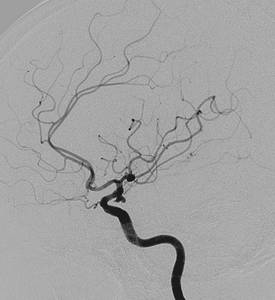

数字减影血管造影技术是一种新的X线成像系统,是常规血管造影术和电子计算机图像处理技术相结合的产物。减影技术的基本内容是把人体同一部位的两帧影像相减,从而得出它们的差值部分;不含造影剂的影像称为掩模像或蒙片,注入造影剂后得到的影像称为造影像或充盈像。广义地说,掩模像是要去减造影像的影像,而造影像则是被减去的影像,相减后得到的影像是减影像。减影像中骨骼和软组织等背景影像被消除,只留下含有造影剂的血管影像。

DSA适用于心脏大血管的检查。对心内解剖结构异常、主动脉夹层、主动脉瘤、主动脉缩窄和分支狭窄以及主动脉发育异常等显示清楚。对冠状动脉也是最好的显示方法。显示颈段和颅内动脉清楚,用于诊断颈段动脉狭窄或闭塞、颅内动脉瘤、动脉闭塞和血管发育异常,以及颅内肿瘤供血动脉的观察等。对腹主动脉及其分支以及肢体大血管的检查,DSA也同样有效。UNt影像园-共享放射医学资源。

数字减影血管造影法是一种建立在图象相减基础上的X线血管造影方法,简称DSA。DSA的基本原理是将注入造影剂前后拍摄的两帧X线图像经数字化输入图像计算机,通过减影、增强和再成像过程来获得清晰的纯血管影像,同时实时地显现血管影。DSA具有对比度分辨率高、检查时间短、造影剂用量少,浓度低、患者X线吸收量明显降低以及节省胶片等优点。